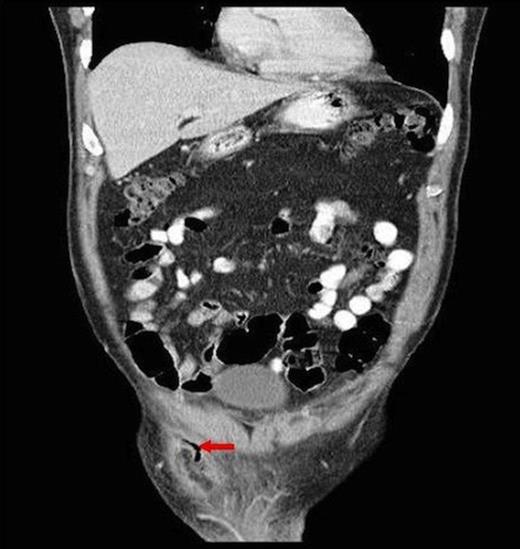

A 61-year old male presented with a 12 hours of right testicular pain, scrotal erythema and raised inflammatory markers (C-Reactive Protein 324 mg/L & leukocytosis 19.9 X 109/L) on background of right inguinal hernia repair 5 years ago and more recent recurring left epididymo-orchitis. He was provisionally diagnosed with right epididymo-orchitis. CT was performed because the pain was extending to the pubic tubercle, previous hernia surgery and markedly raised inflammatory markers. This showed an acutely inflamed appendix within a small recurrent direct inguinal hernia, entering the scrotum with surrounding inflammatory soft tissue (Figure 1, 2).

Axial CT showing luminal air of appendix segment in the scotum (arrow)